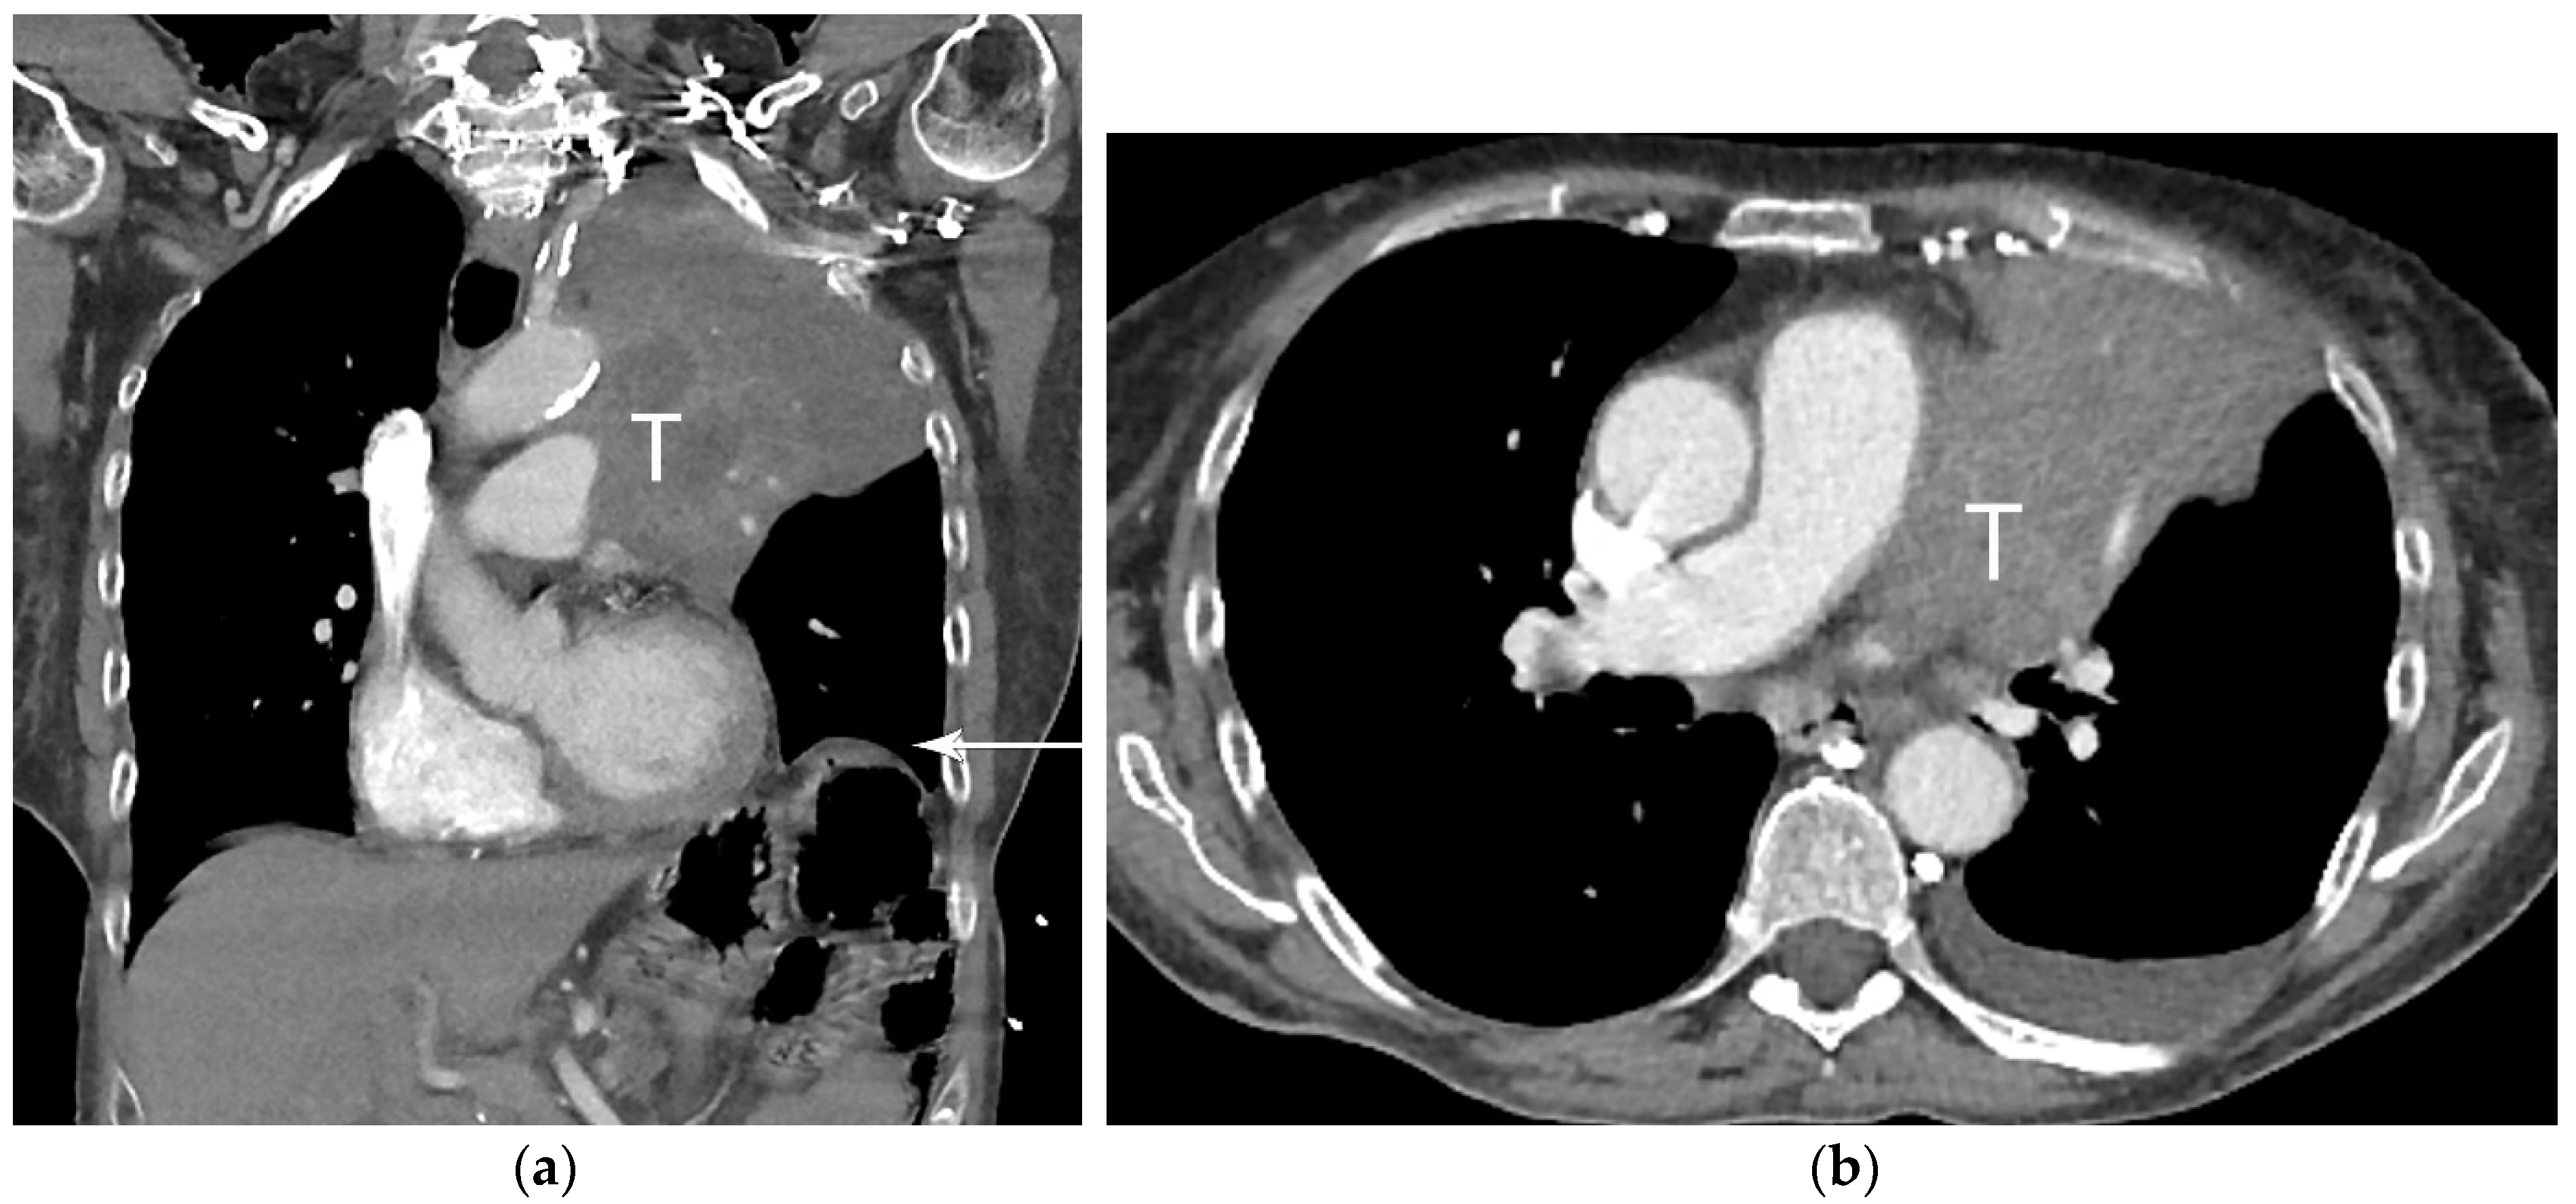

2. T Classification